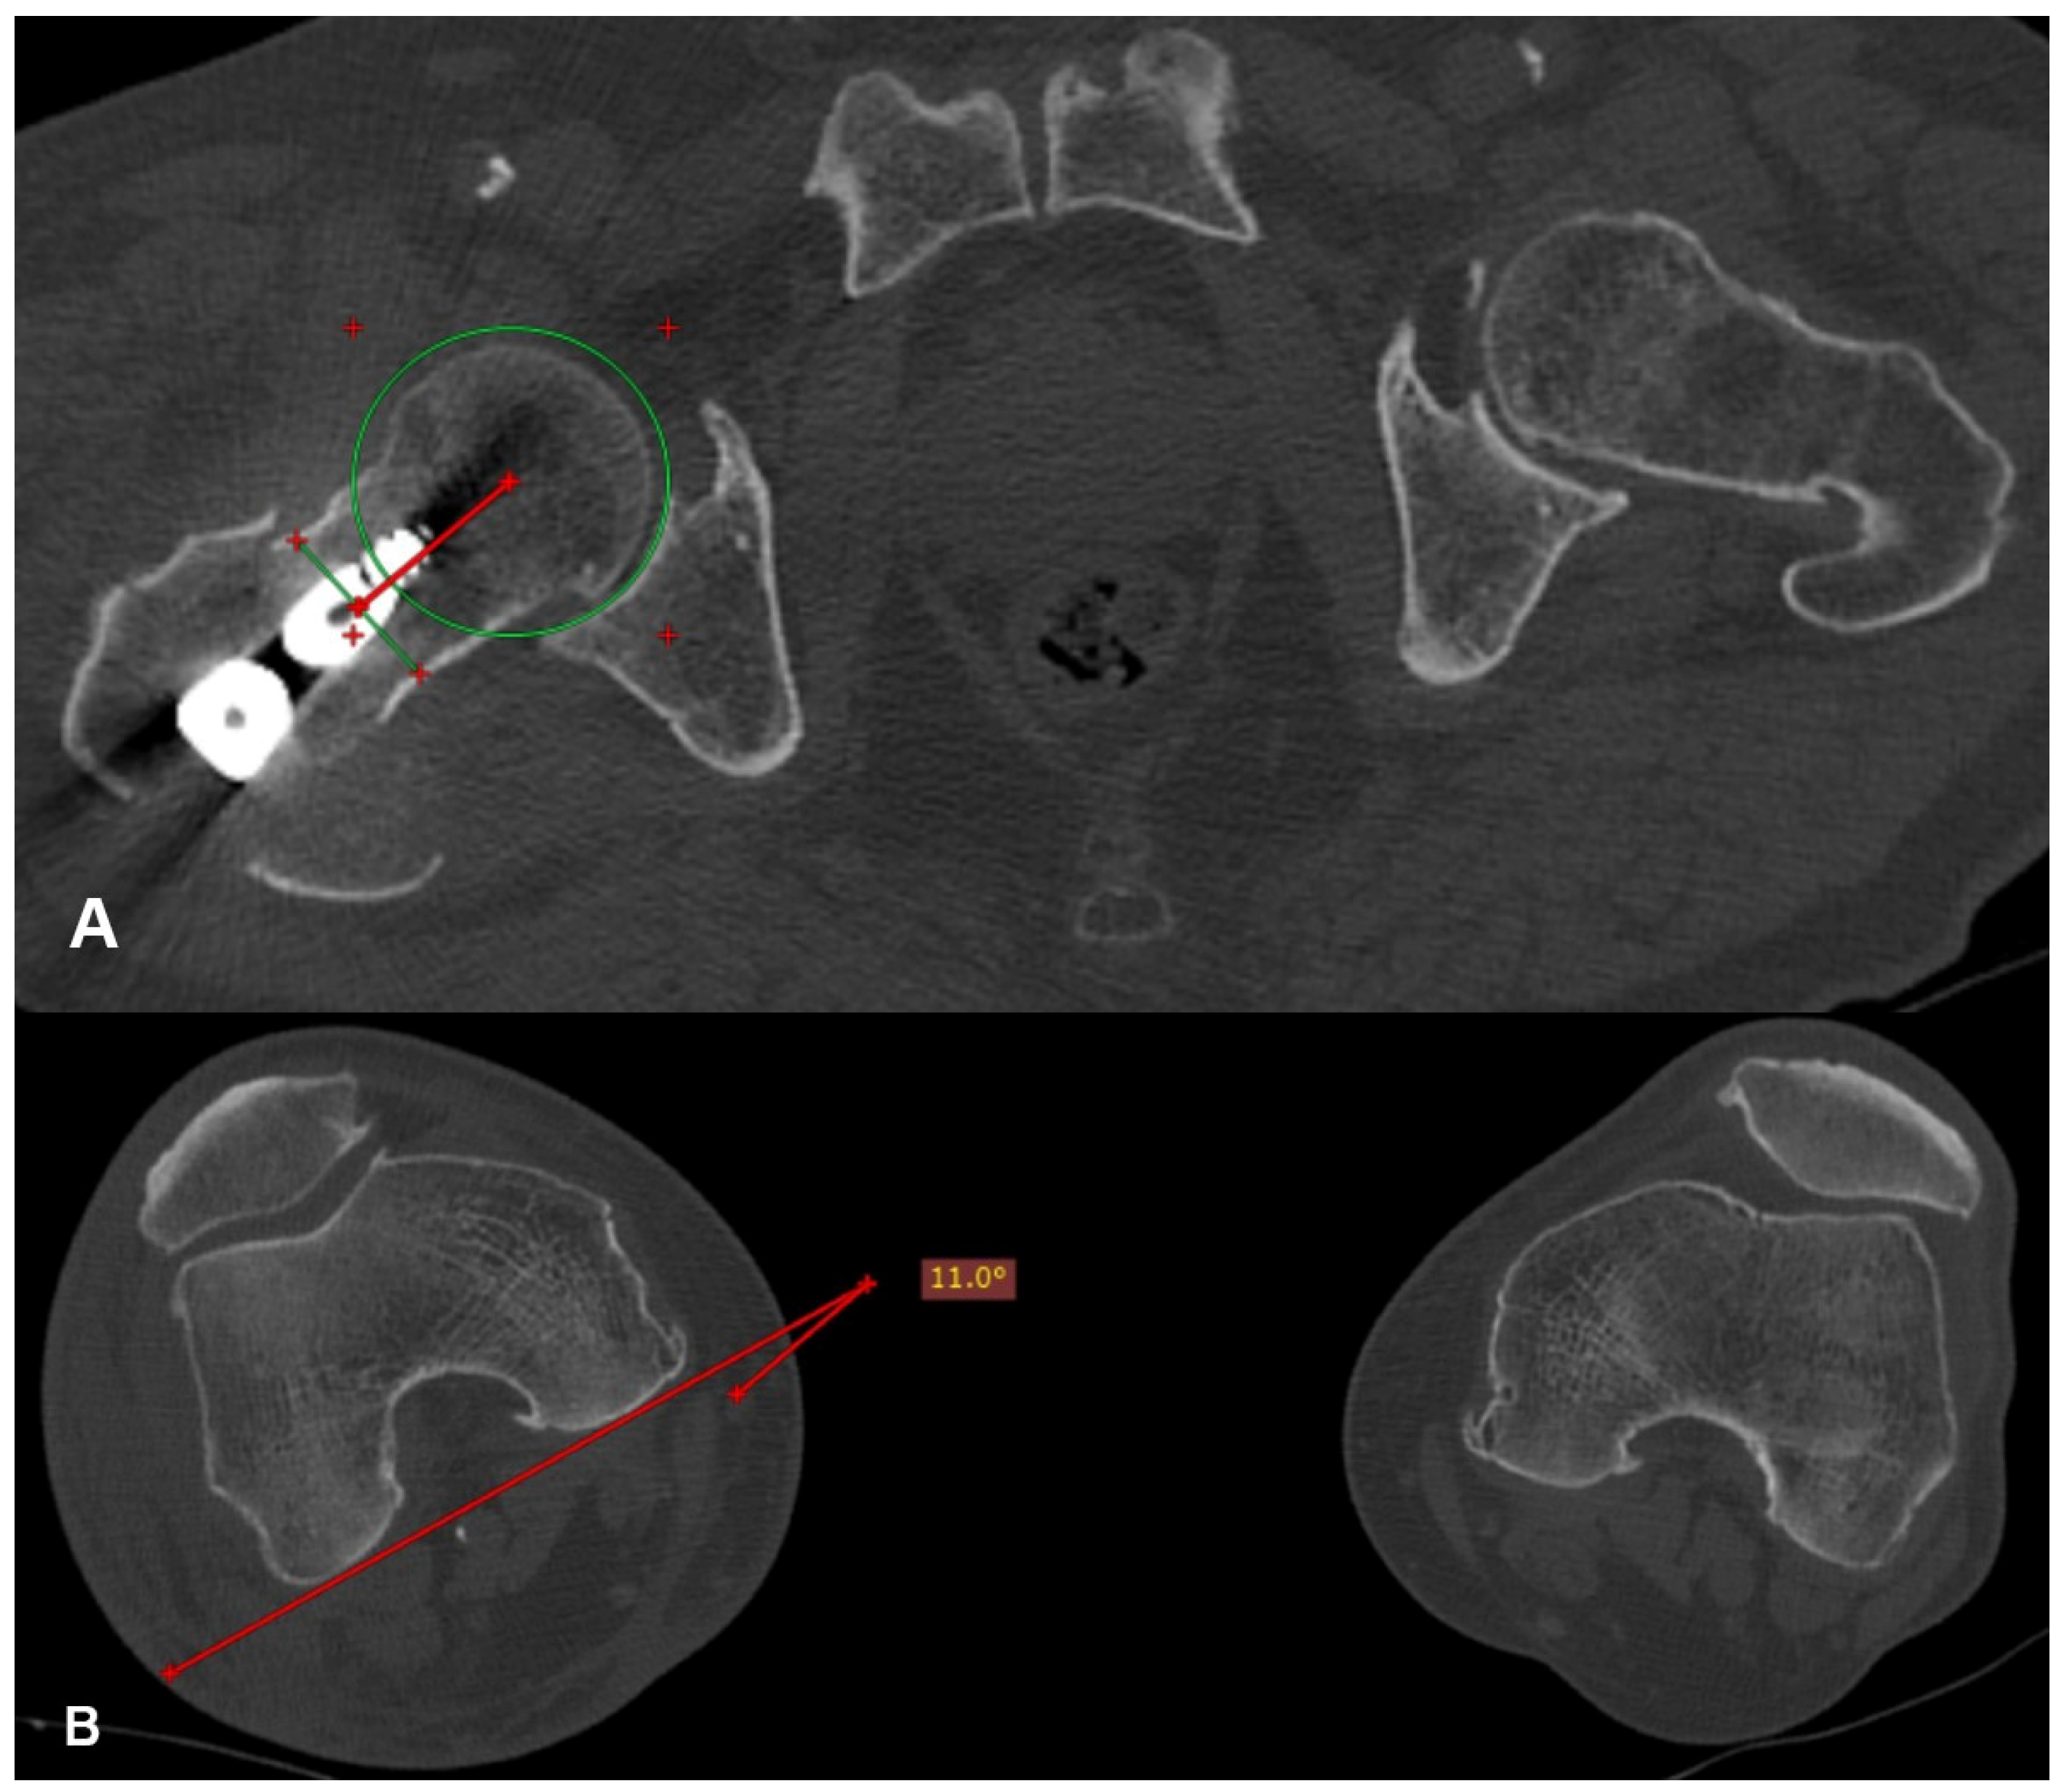

Each patient underwent a computed tomography (CT) scan of the hips and knees postoperatively after signing an informed consent and when they were pain free. The femoral anteversion of the operated and healthy hip, as well as the femoral anteversion difference between them (D angle), were calculated on the CT scan (Figure 2) using the method described by Jeanmart et al. in 1983 [11].

Figure 2.

(A) A line is drawn that connects the center of the head, in the transverse section where it presents its maximum diameter, with the center of the neck, in the transverse section where it presents its narrowest width (redline). (B) Femoral anteversion is the projective angle formed between the tangent line at the posterior femoral condyles and the line connecting the center of the head with the center of the neck (red lines).